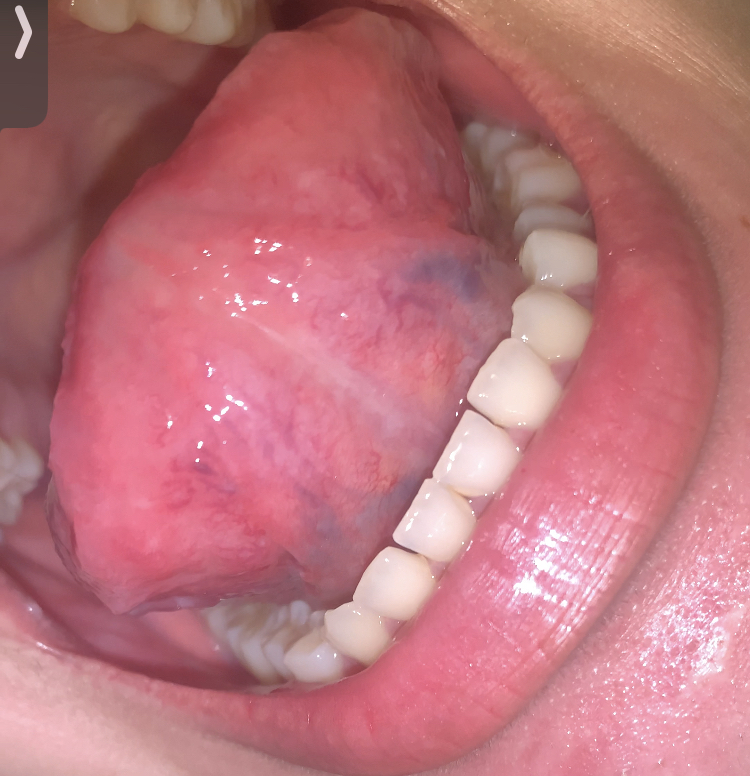

13 พฤษภาคม 2568 00:19:41 #1 สวัสดีค่ะ เคยมีความเสี่ยงติดเชื้อหูดหงอนไก่มาเมื่อหนึ่งปีที่แล้วค่ะ เคยขึ้นบริเวณอวัยวะเพศแต่ไม่มั่นใจว่าที่ปากมีขึ้นหรึเปล่า จากรูปเป็นตุ่มรับรสปกติมั้ยคะ หรือเป็นหูดขอบคุณค่ะ https://haamor.com/media/create_topic/20250513001048.jpeg https://haamor.com/media/create_topic/20250513001536.jpeg https://haamor.com/media/create_topic/20250513001806.jpeg https://haamor.com/media/create_topic/20250513001852.jpeg

13 พฤษภาคม 2568 18:27:02 #2 ไม่เห็นมีหูดหงอนไก่เลยครับ เป็นตุ่มรับรสปกติครับ |